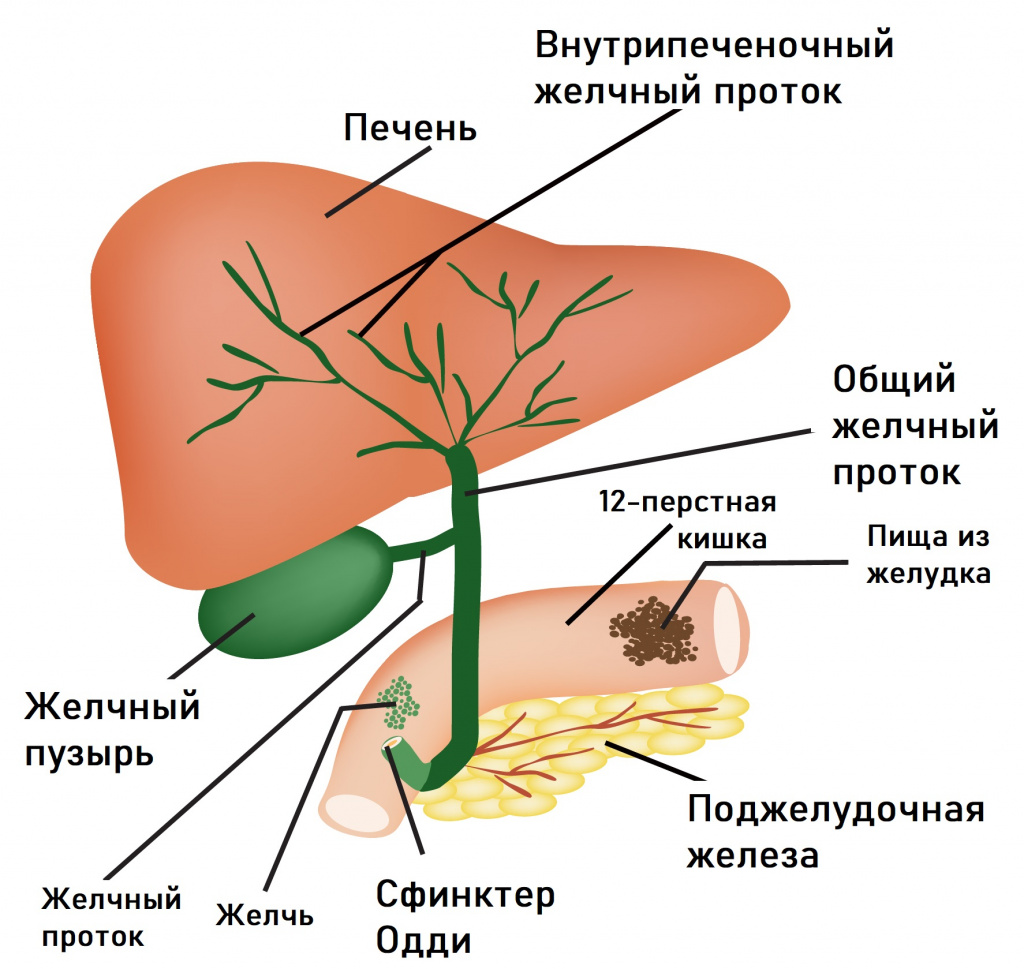

Анатомия и особенности Гартманова кармана желчного пузыря